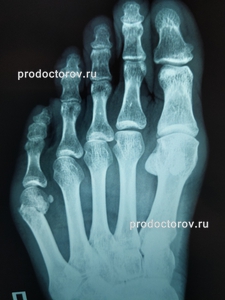

Обратилась к Кириллу Базаровичу с переломом 5 плюсневой кости со смещением отломков (перелом был уже недельной давности). Доктор оперативно принял решение об операции, и уже через 1,5 суток (16 октября 2019 г.) была проведена ювелирная операция с установкой пластины. Доктор до операции и после постоянно был со мной на связи на случай возникновения вопросов. Это абсолютный профессионал своего дела! При выписке лично дал мне все рекомендации и предостережения, разрешил связаться с ним в любой момент. Хочется также поблагодарить персонал стационара, а именно анестезиолога (смена 16.10.2019) - не отходил от меня ни на секунду, был абсолютно внимателен ко всем нюансам во время и после операции, сестру-анестезиолога Елену Ивановну (смена 26.10.2019) - она поддерживала меня до, во время и после операции (гладила по голове, подбадривала, была внимательна к моим просьбам); также хочу поблагодарить медсестру (к сожалению, не знаю ее имени), которая ассистировала хирургу во время операции; отдельная благодарность Репину Игорю Викторовичу, его внимательность ко мне во время (контроль операции рентгеном) и после операции была мне очень приятна и нужна, дал мне много рекомендаций, делал абсолютно безболезненные и деликатные перевязки (золотые руки), всегда видела его в хорошем настроении и с дружелюбным настроем, он также был чуток к любой моей просьбе. Спасибо медсёстрам с поста во время смен (16.10-18.10) - внимательные, добрые. Очень хорошее впечатление у меня о пребывании в данном стационаре и о таких чудесных людях. Благодарю вас!